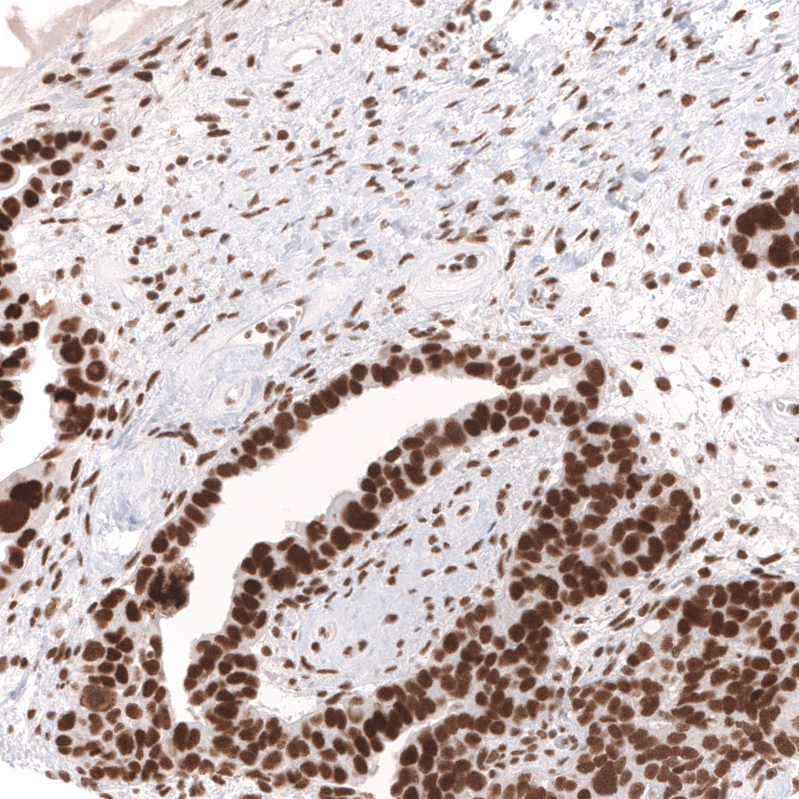

Immunohistochemical staining of human cerebral cortex shows strong nuclear positivity in neurons.